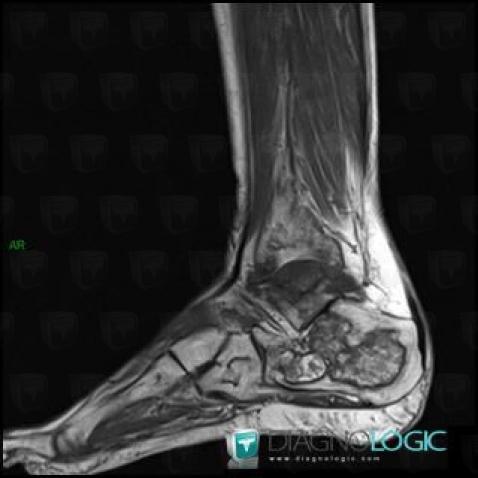

Avascular necrosis, Tibia - Distal part, MRI

Here is the specific information in the key image above:

- Diagnosis Avascular necrosis, Location(s) Tibia - Distal part, with gamuts Well-defined osteolysis, Epiphyseal osteolysis

- Diagnosis Gaucher disease, Location(s) Tibia - Distal part, with gamuts Mulltiple osteolysis

Avascular necrosis, Calcaneus, MRI

- Diagnosis Avascular necrosis, Location(s) Calcaneus, with gamuts Osteolytic lesion of calcaneus, T1 WI Hyperintense bone lesion, Lucent lesion in foot

Avascular necrosis, Talus, MRI

- Diagnosis Avascular necrosis, Location(s) Talus, with gamuts T2 WI Hypointense bone lesion